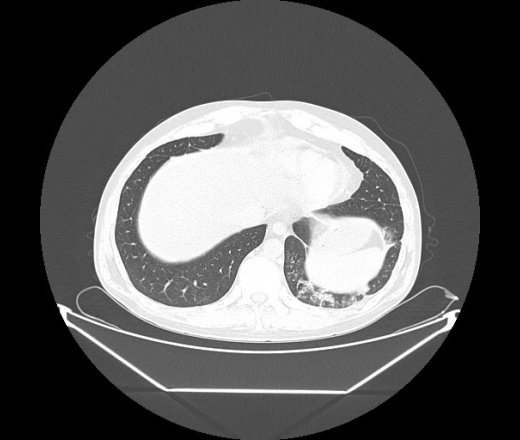

М. 1984 г.р.  Лихорадка 39, кашель , одышка.. и надоевший всем вопрос- "типично ли для ковид?" ( в настоящее время на него обязательно нужно дать ответ в своем протоколе)

На мой взгляд нетипично для ковид: много центрально-расположенных поражений, лобарное поражение нижней доли слева. 50/50

Не типичая картина для ковид.

КТ-признаки двусторонней бактериальной пневмонии.

Все верно, здесь абсолютно нетипичная картина, несмотря на матовое стекло с ретикулярными изменениями, но почему-то  посчитали иначе. Кстати,  "малыша" не заметили)?

Добавил 6 день

Что за малыш? Будущий абсцесс? Не заметил. Только о туберкулёзе подумал

+ 1?  Зона очень похожа была на формирующийся абсцесс, даже по рентгенпризнакам. Еще хотела спросить, но постеснялась. А на контроле видно

да, это я о абсцессе.